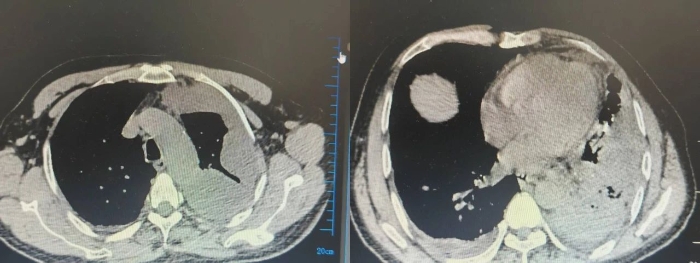

术前CT影像

患者入院时,初步诊断为肺脓肿合并脓毒血症、脓胸,出现高热症状,心率偏高,且气道内咳出较多脓痰。呼吸与危重症医学科立即成立呼吸治疗抢救组,给予床旁支气管镜下吸痰及抗感染、化痰、补液、营养支持等治疗,患者病情暂时稳定。